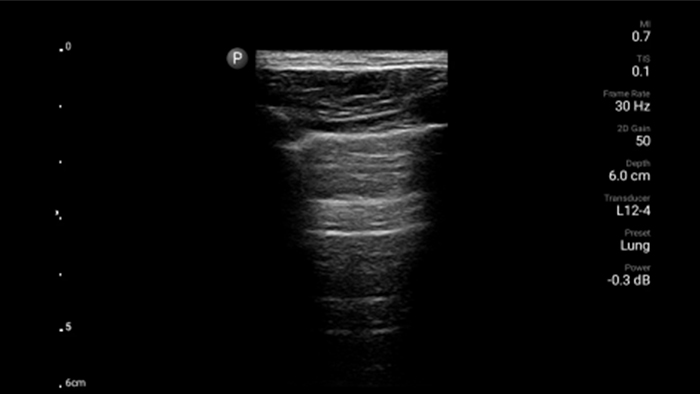

Lumify handheld ultrasound offers images that enhance diagnostic confidence.

See more when it counts

Lumify can help you make real-time decisions with more confidence, from assessment to recovery. Reveal the subtle details of an image, uncover enriched tissue definition with multiple angles and much more.